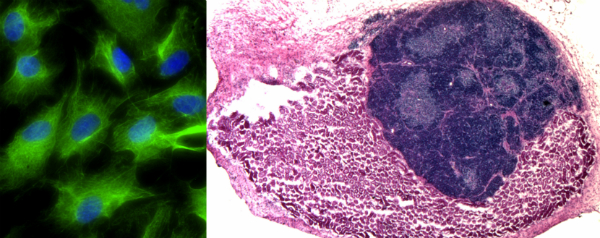

De thymus is een klein orgaantje vlakbij het hart. In dit orgaan ‘rijpen’ de T-cellen, een bepaald type afweercellen. De wetenschappers haalden fibroblastcellen, die een grote rol spelen bij het vormen van bindweefsel, uit muizenembryo’s en manipuleerden die zo dat ze veranderden in thymuscellen. De cellen veranderden daardoor niet alleen van vorm maar gingen ook T-cellen produceren. De gemanipuleerde cellen plaatsten ze in een muis. Daar groeiden ze uit tot een nieuw orgaan.

Beeld: MRC Centre for Regenerative Medicine, University of Edinburgh